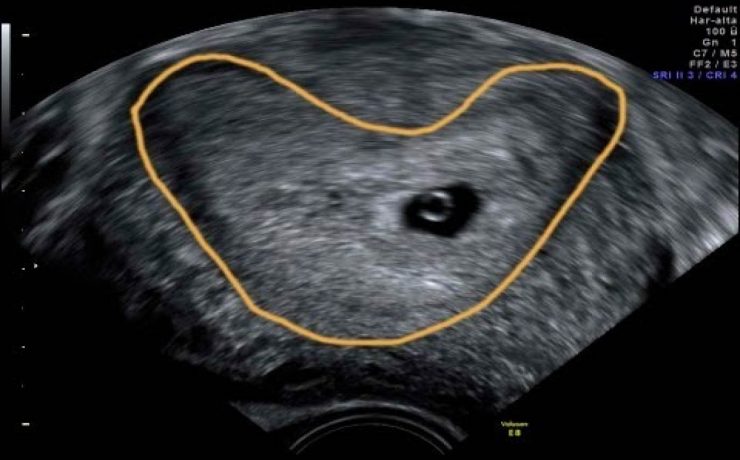

Durante el embarazo y la lactancia, la mama puede verse afectada por una variedad de trastornos únicos y específico, incluyendo trastornos benignos, relacionados con los cambios fisiológicos, inflamatorios, enfermedades infecciosas, papilomatosis juvenil y tumores benignos y malignos. Pacientes con carcinoma de mama asociada al embarazo presentan diagnóstico de neoplasias avanzadas y